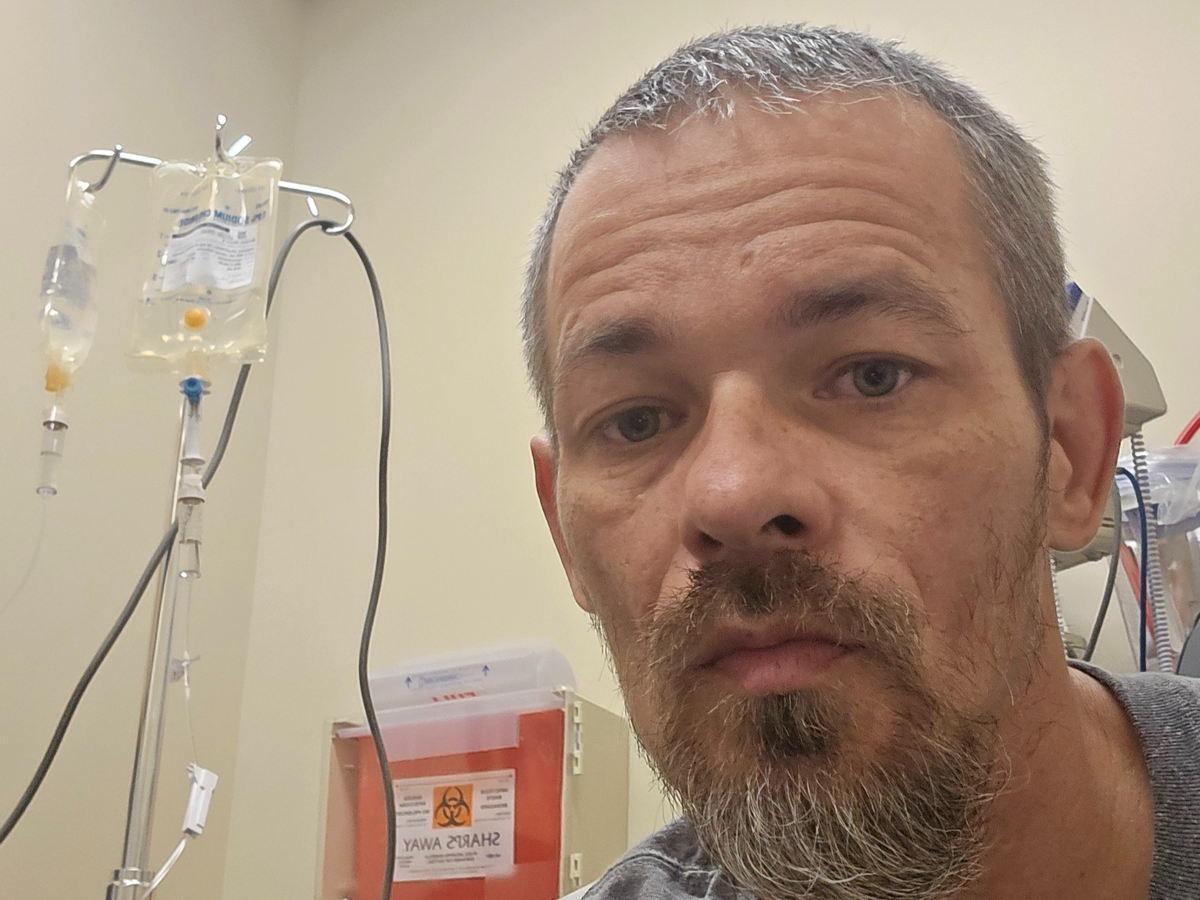

My name is Shane, and on October 30th, I was diagnosed with metastatic poorly differentiated non keratinizing squamous cell carcinoma. Since then, my life has changed dramatically. I am currently undergoing weekly chemotherapy and daily radiation treatments, which has made it impossible for me to work. The physical and emotional toll of treatment is challenging, and the uncertainty about my health and future can feel overwhelming at times.

Because I am unable to work, I am struggling to keep up with my bills and the cost of gas to get to my appointments. Every day is focused on fighting this cancer and making it to my treatments, but the financial stress adds another layer of difficulty. I am reaching out for help so I can cover essential expenses and focus on my recovery without the constant worry about how I will pay for basic needs for me and my kids .